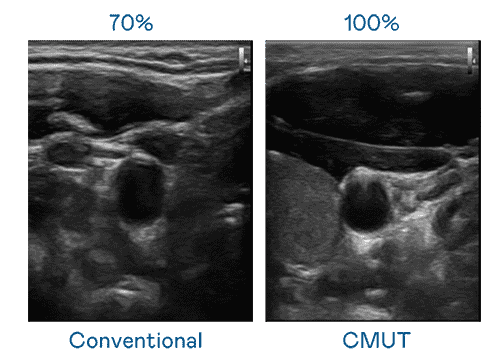

CMUT 技术是一种用电容式微机电元件来产生超音波讯号的技术。。。。与传统 PZT 压电式技术相比,,CMUT 频宽增加 30%,,更宽频的超音波讯号让影像解析度大幅提升,,是实现高影像品质医疗超音波扫描、、促进精准医疗发展的关键技术。。。

超音波影像的解析度高低,,,,首先取决于探头能发出的讯号频宽。。。尊龙集团 CMUT 可提供高清晰的超音波讯号,,,提供高频宽、、、、高灵敏度、、影像纹理细节更高的超音波影像,,,,协助医护人员缩短影像判读时间及利用精准的医疗影像进行诊断。。。。